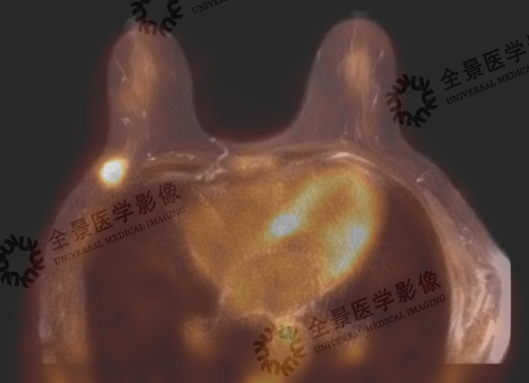

一站式检查可采集到多设备影像数据,并对数据按照同一体位和床位进行融合分析,为医生的准确诊断提供了扎实的信息基础。

列举了我中心基于一站式扫描的影像融合案例。如乳腺结节定性,乳腺微小病灶检出及定性,浸润性导管癌分期,浸润性导管癌与乳腺纤维瘤良恶性鉴别等。

案例展示: